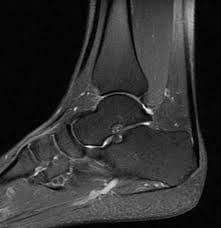

End ankle pain! Accurate diagnosis and rapid treatment with high-resolution Ankle MRI imaging. Expert radiologists, modern medical imaging center.